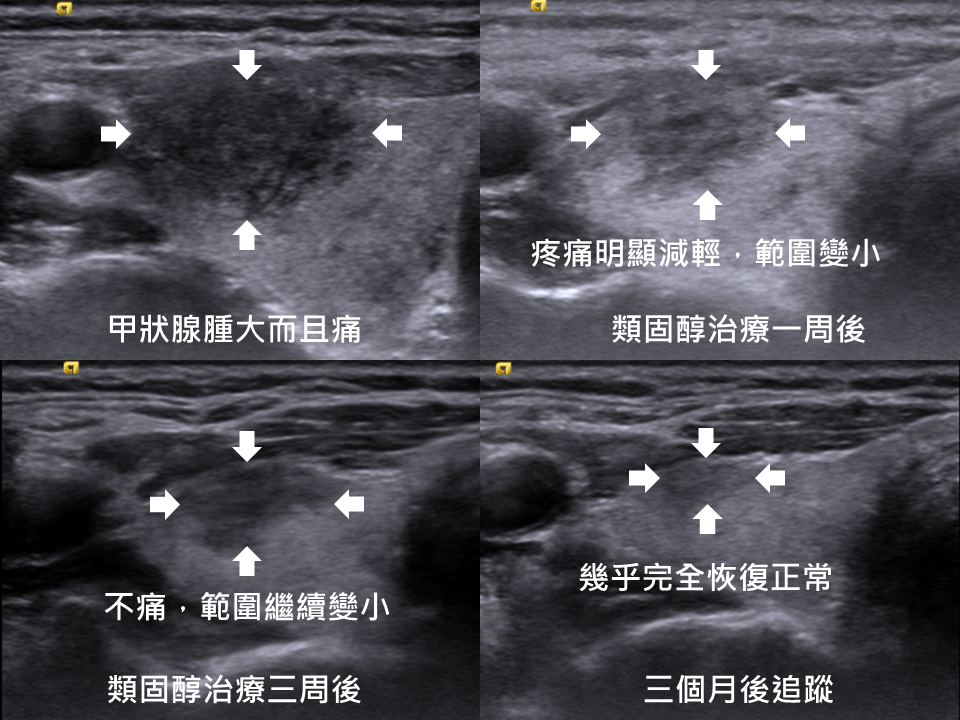

個案分享(使用類固醇治療)

一開始抱怨右側脖子痛而且腫脹,類固醇治療一週後,症狀大幅度改善。繼續給予兩週的類固醇,完全不痛,而且也覺得消腫很多。之後就停藥,請病人三個月後來追蹤,超音波幾乎完全恢復正常。